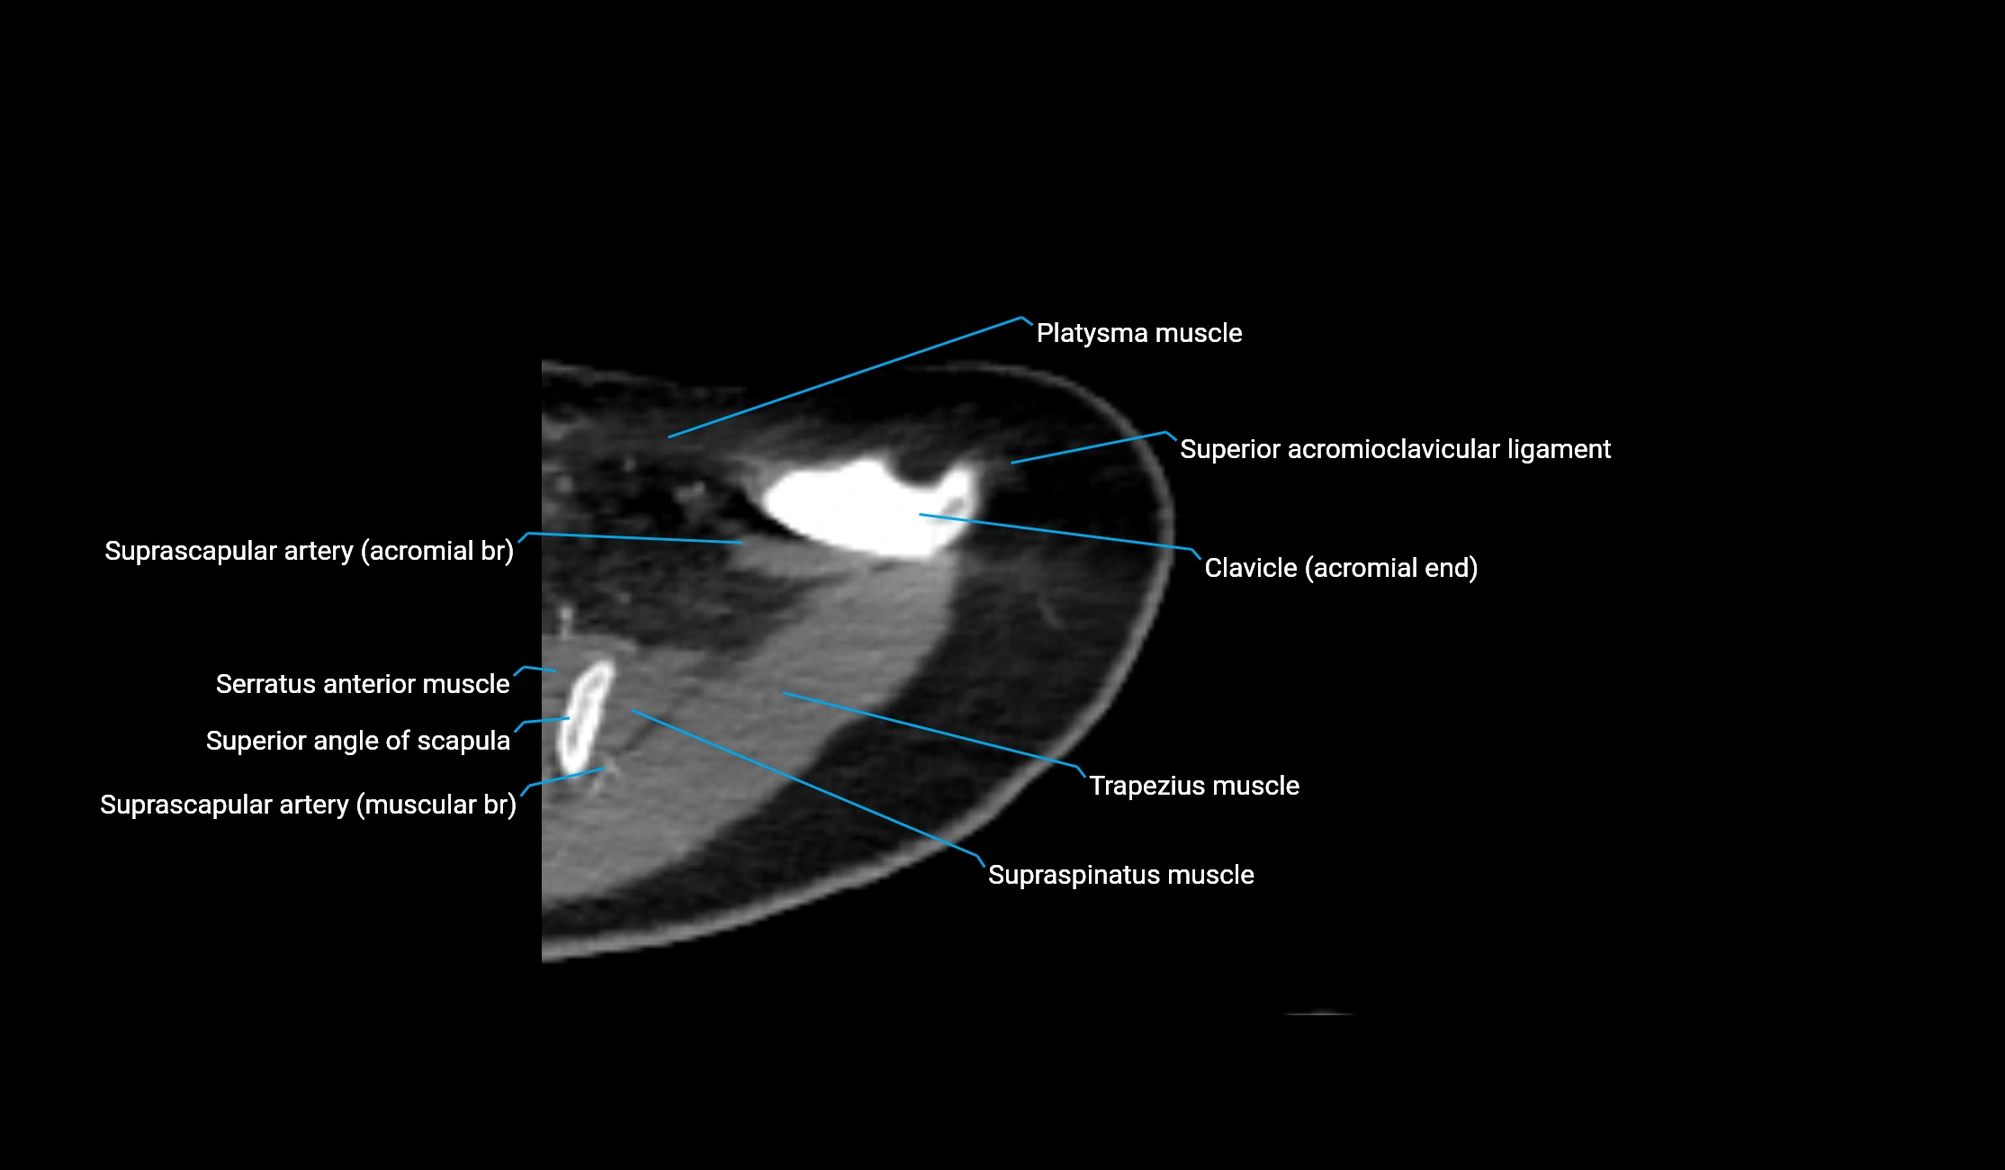

CT image